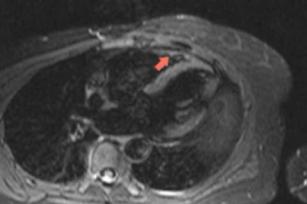

Diagnosing Takotsubo cardiomyopathy with the help of CMR 4th Oct 2017 - Andrew R. Houghton, MD Learn how to diagnose Takotsubo cardiomyopathy with the help of cardiac MRI. Taken from our CME accredited CMR ...